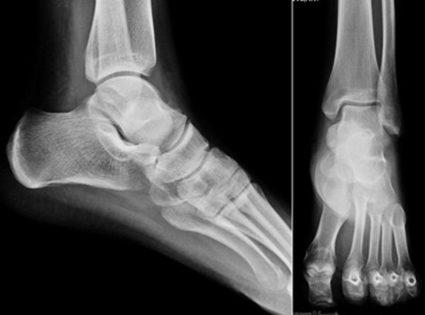

Диагноз выставляется на основании жалоб пациента, анамнестических данных, результатов внешнего осмотра и инструментальных исследований. Наиболее информативна рентгенография. На полученных изображениях отчетливо визуализируются изменения структуры костных, хрящевых тканей, характерные для подагры, деформирующего артроза, некоторых видов артрита.

С помощью МРТ и КТ можно оценить состояние соединительнотканных структур, кровеносных сосудов, нервов. При подозрении на инфекционный процесс проводятся биохимические исследования для установления видовой принадлежности патогенных микроорганизмов.